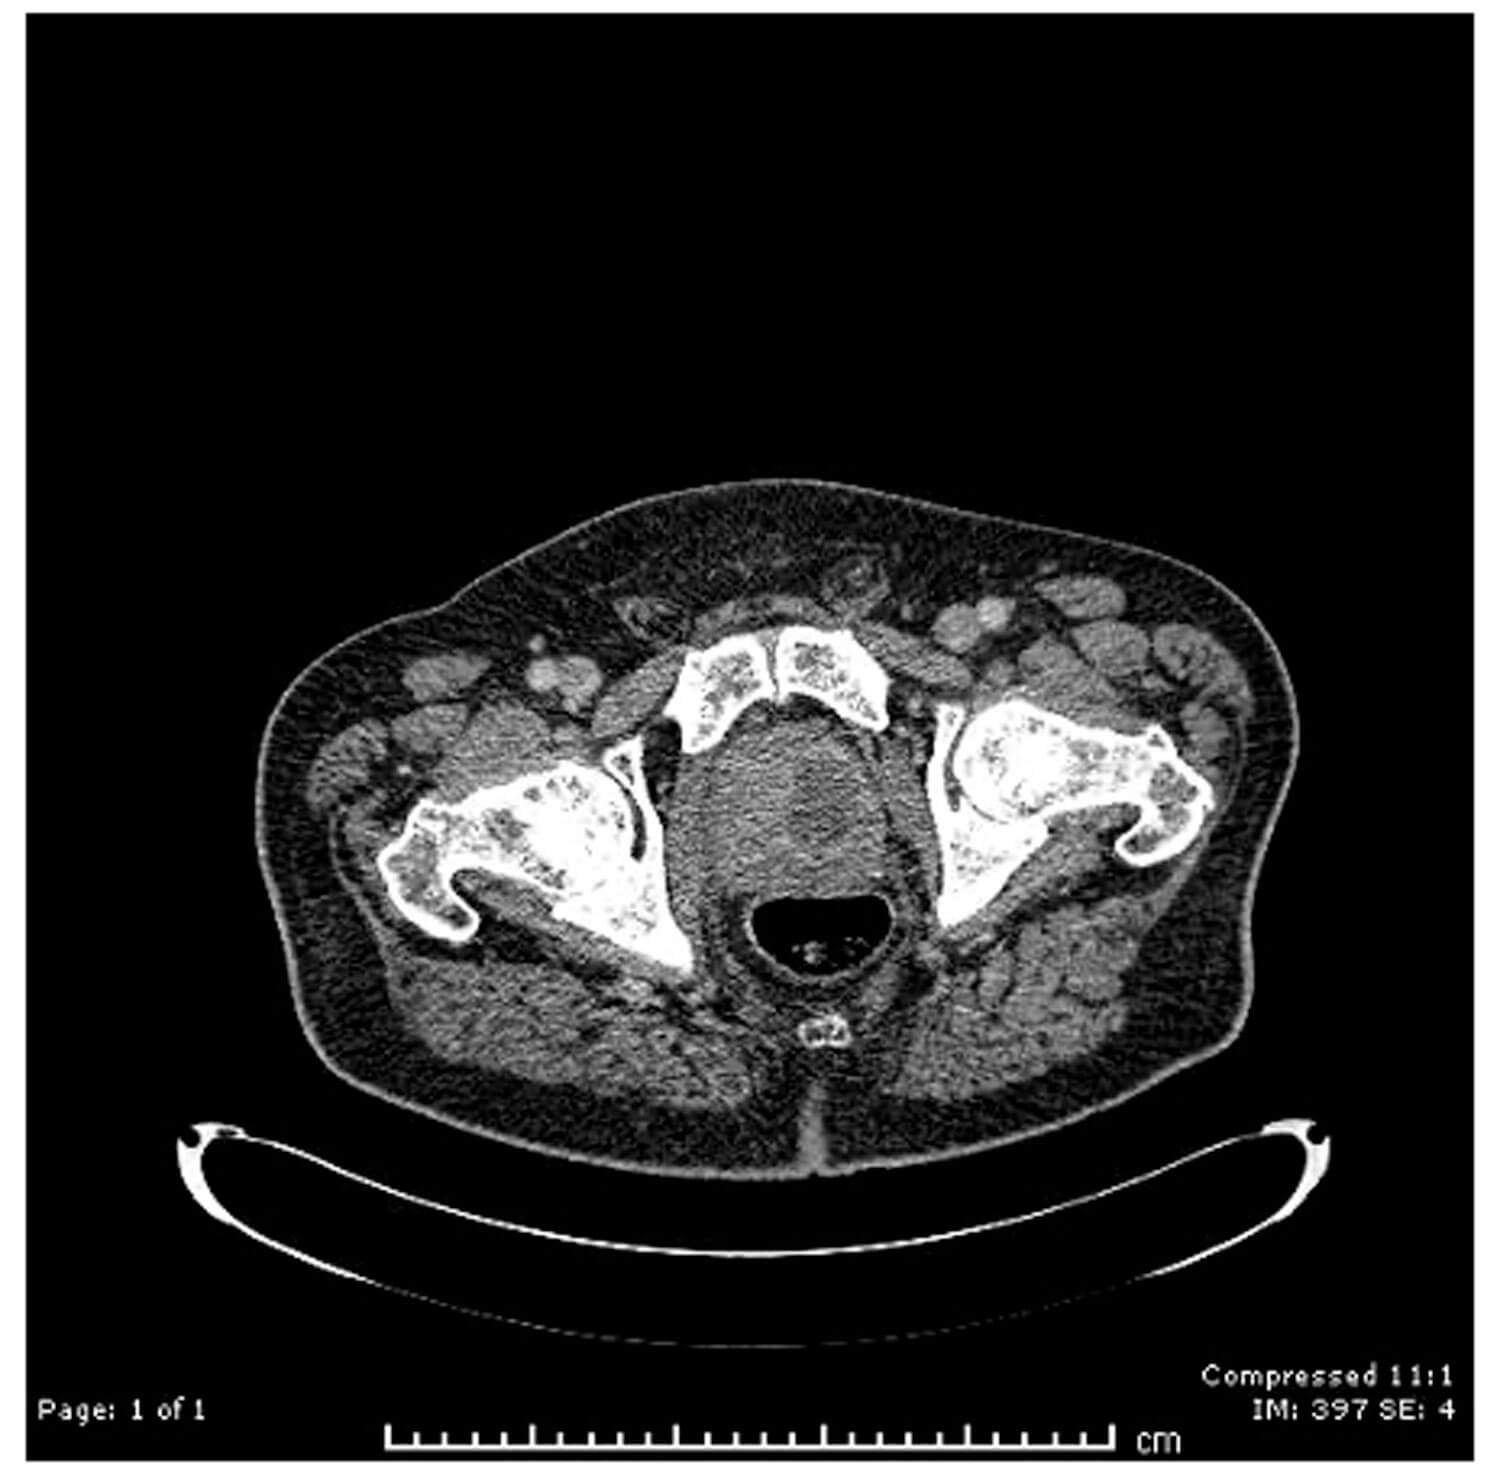

An 72-year-old male patient presented with fever and perineal pain of a few weeks’ duration. He was known to have LUTS and was on tamsulosin but was otherwise fit and well. Mid-stream urine sample showed no growth. Blood culture grew Citrobacter koseri, sensitive to IV Tazocin. However, the patient was not responding to IV antibiotics over 48 hours. CT of the abdomen and pelvis revealed a left prostate lobe abscess, localised to the transitional zone (Figure 1a and b). The patient was treated with transurethral deroofing under general anaesthetic (Figure 2) and was clinically well and discharged two days later on oral Augmentin® and trial without a catheter in 10 days. The patient was seen four weeks later in the outpatients department and was discharged having been judged to be making a good recovery.

Figure 1a: CT abdomen / pelvis (coronal), left prostate abscess, low attenuation.

Figure 1b: CT abdomen / pelvis (sagittal), left prostate abscess.

Unlike TRUS, which is intrusive and may be painful, CT provides non-invasive cross-sections that may be reconstructed into 3D images. Many patients find CT scanning to be more acceptable consequent to the pain associated with TRUS in PA. PA is characterised on CT by well-defined, low-attenuation areas within one or more prostate lobes. CT is also able to exactly define the extra glandular extent of the fluid collection, which may extend into the ischiorectal fossa and perirectal tissue [14].